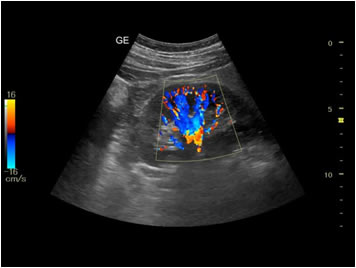

Vascular Doppler Scan

Your doctor may suggest a Doppler ultrasound exam if you show signs of decreased blood flow in the arteries or veins of your neck, arms or legs.

A reduced amount of blood flow may be due to a blockage in the artery, a blood clot inside a blood vessel, or an injury to a blood vessel. This can help to screen people who are at risk of strokes, heart attacks and pulmonary embolism(blood clot travelling to the lungs).